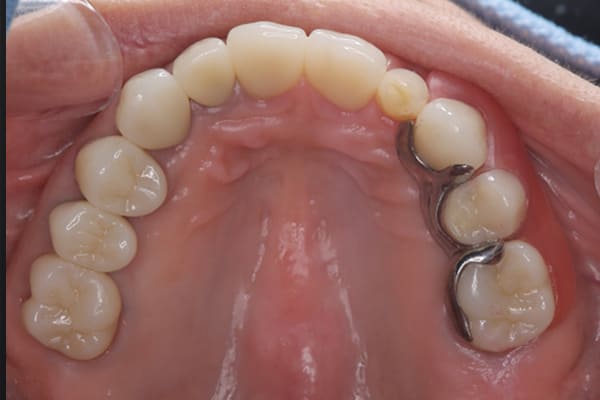

- 上顎精密金属床部分入れ歯

- ジルコニアクラウン3歯

- 上顎精密金属床部分入れ歯:55万円

(ミリング、ラベット加工込み) - ジルコニアクラウン:11万円×3歯

合計:88万円(税込)

上あごに接する入れ歯に違和感がありになっていたとのことで、プラスチックが大きく削られた入れ歯をされていました。

そのため入れ歯の安定が悪く、お食事の際に入れ歯が動き、がたつきを感じられている状態でした。

前歯にバネにより見た目の問題も抱えておられました。

かみ合わせが低くなった歯を本来の高さに戻し、保険では使用できない歯に負担のかかりずらいバネで、歯の保存、審美性を確保しました。

前歯にバネを設定せず、見えない奥歯に維持力をもたせたバネを用い、またバネのかかる歯の負担軽減を目的に、被せ物は繋げることで強度を増す設計とすることで、入れ歯が動かずガタつき、審美性不良が解消されました。

入れ歯を修理する中で、入れ歯の上あごの接触面積ではなく、厚みに対しての違和感と診断し、薄い金属を用いた従来の厚みを1/3程度にした入れ歯にすることにより違和感は消失しました。